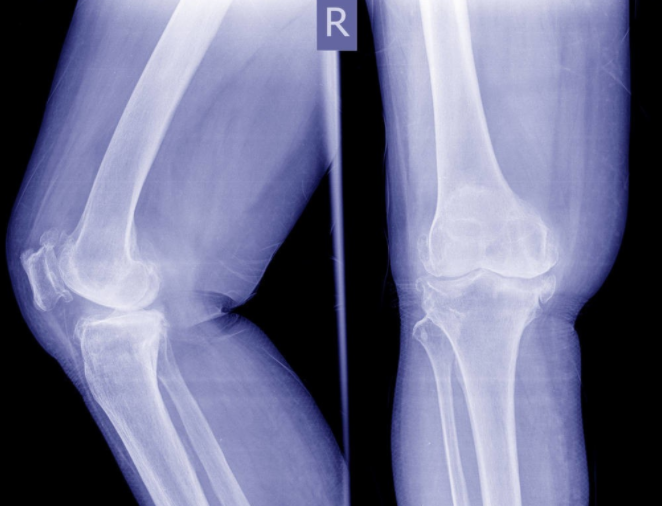

1、膝关节退化、关节疾病

人体的膝关节表面覆有一层软骨,可以帮助人体灵活地屈伸膝关节,保护膝关节避免受到直接的侵害。随着时间的推迟和使用过度等原因,软骨会逐渐磨损退化。严重者关节软骨可能会脱落,导致膝关节的能力减弱,出现退行性关节炎。

同时骨关节也可能会因为病毒、细菌感染,出现风湿类的关节疾病。一旦患上这类疾病,不仅患者会感到关节部位疼痛难忍,还会损伤到关节,导致关节病变,加速骨关节的退化。这也是老年人之所以会下肢无力的原因。